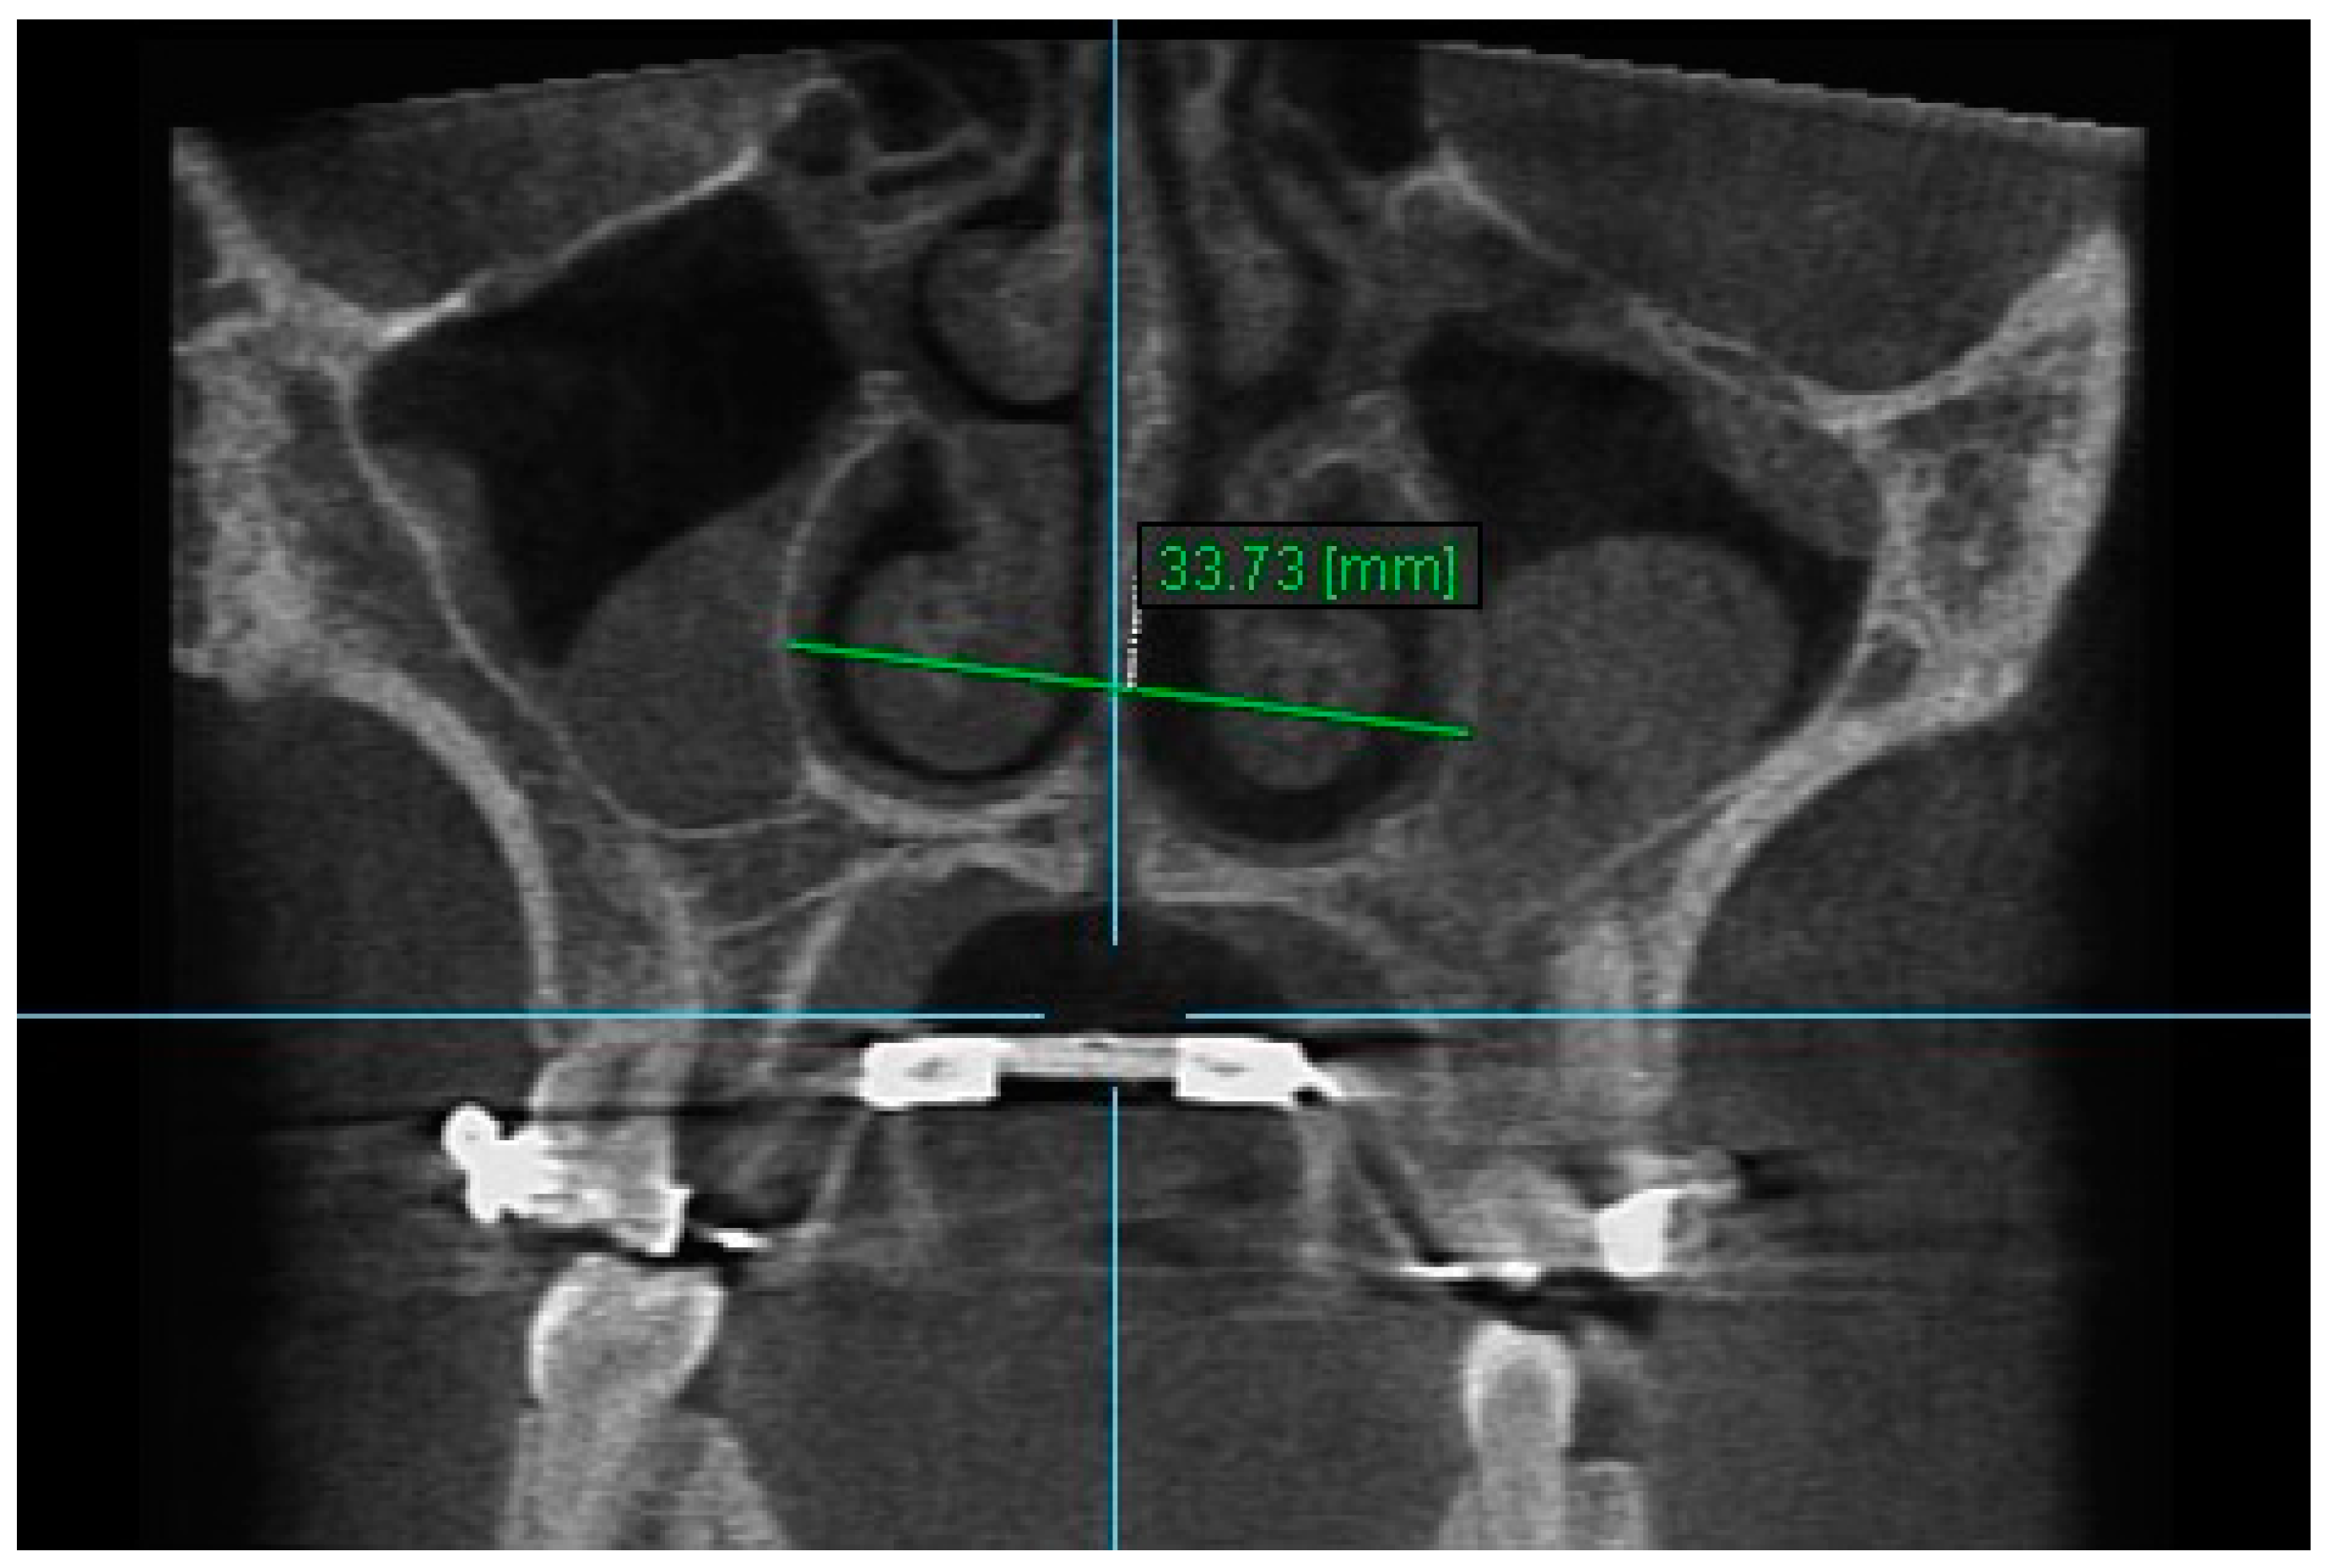

2. Nasal Width 2: The maximum lateral interior width of nasal cavity on coronal slice through the center of the root of the second premolar (Figure 4).

Figure 4.

Nasal Width 2.